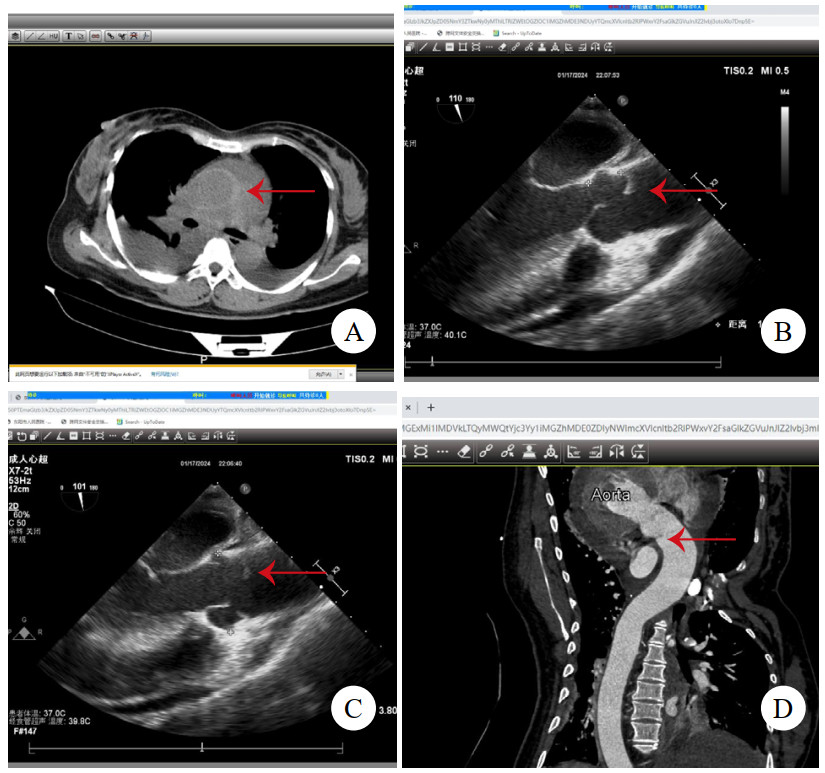

1 病例资料病例1,女,41岁,因“突发严重胸闷气促15 h”入院。发病后立即就诊于附近医院,查胸腹平扫CT提示急性肺水肿、双侧胸腔积液、心包积液,查血红细胞计数3.38×1012/L,肌酐369 μmol/L,乳酸11.7 mmol/L,钠尿肽超过检测上限,立即转诊至本院。考虑存在急性多脏器衰竭,立即收入重症监护室,因少尿予连续肾脏替代治疗。右侧胸腔穿刺引流液红细胞计数高达0.22×1012/L。床边经胸超声心动图(transthoracic echocardiography, TTE)未见主动脉病变,但见左心室弥漫肥厚符合高血压性心脏病,心包大量积液伴血块,且出现心包填塞,紧急行心包穿刺,但置管后引流不畅。因心包积液病因不明,且回顾前平扫CT可见升主动脉壁局部密度增高(图 1A),急查主动脉CTA,但影像科对升主动脉根部管壁褶皱情况考虑为搏动伪影。后查经食管超声心动图(transesophageal echocardiography, TEE),清晰可见升主动脉直径38 mm,距主动脉瓣环约16 mm处有飘动纤细光带,考虑升主动脉LIT(图 1B、图 1C)。遂行急诊开胸手术,术中见心包腔内大量积血并血块,升主动脉外膜血肿延入肺动脉外膜至右侧肺门。建立体外循环后,在头臂干开口近侧阻断升主动脉,顺行灌注心脏停搏液良好,纵行切开升主动脉,见左右冠瓣上方横行内膜裂口,中膜无假腔形成,冠状动脉开口、主动脉瓣无病变。用26 mm人工血管置换升主动脉,手术顺利。术后复查TTE见人工血管通畅、形态良好。回顾并重建术前主动脉CTA,曲面重建可见内膜片(图 1D),该处主动脉直径为37 mm。患者术后肾功能衰竭持续,规律随访血透,6个月后失访。

| 注:A为平扫CT,箭头示升主动脉壁增厚、密度增高;B为TEE舒张期,箭头示飘动纤细光带;C为TEE收缩期,箭头示飘动纤细光带;D为主动脉CTA,曲面重建,箭头示内膜片 图 1 例1患者两次CT及术前TEE影像 |